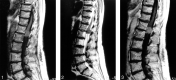

Sagittal T1-weighted MR image shows the spinal cord tumor at the level of the conus medullaris, which has a slight and homogeneous signal hyperintensity relative to that of the cord. fig 2. Sagittal T2-weighted MR image shows that the mass, compared with the spinal cord, is somewhat hypointense. fig 3. Sagittal contrast-enhanced T1-weighted MR image shows mild homogeneous enhancement in the tumor